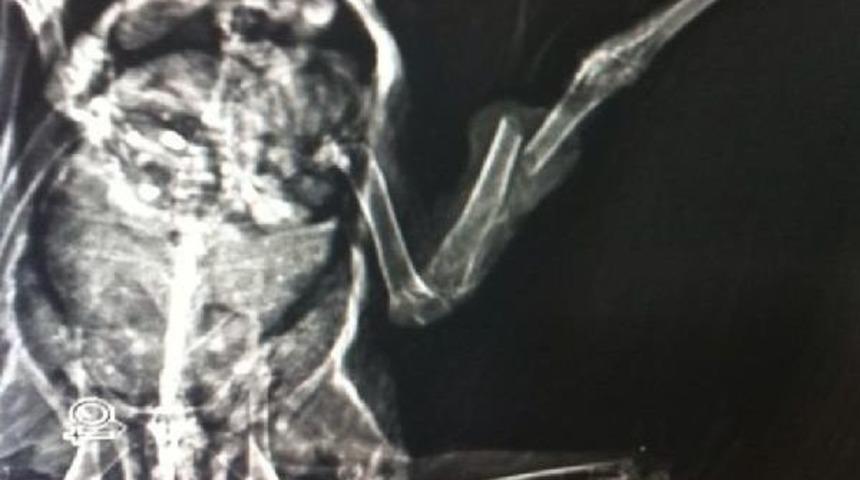

Durmuş SEVİNDİK/ZONGULDAK, Bir vatandaş, caddede yürüyemeyen güvercini alıp Zonguldak Veteriner Tıp Merkezi'ne götürdü. Yapılan kontrolde güvercinin sağ bacağında kırık saptandı. Yaklaşık 1 saat süren operasyonla güvercinin bacağına platin takıldı. Veteriner Önder Alkan, güvercinin sağlığına kavuştuğunu ve tekrar aynı kişiye teslim edildiğini söyledi. Alkan, "Güvercinin kanatları sağlam. Uçmasına bir engel yoktu ama bacağı kırık olduğu için yürüyemiyordu. 20 gün sonra inşallah yürümeye başlayabilir" dedi.